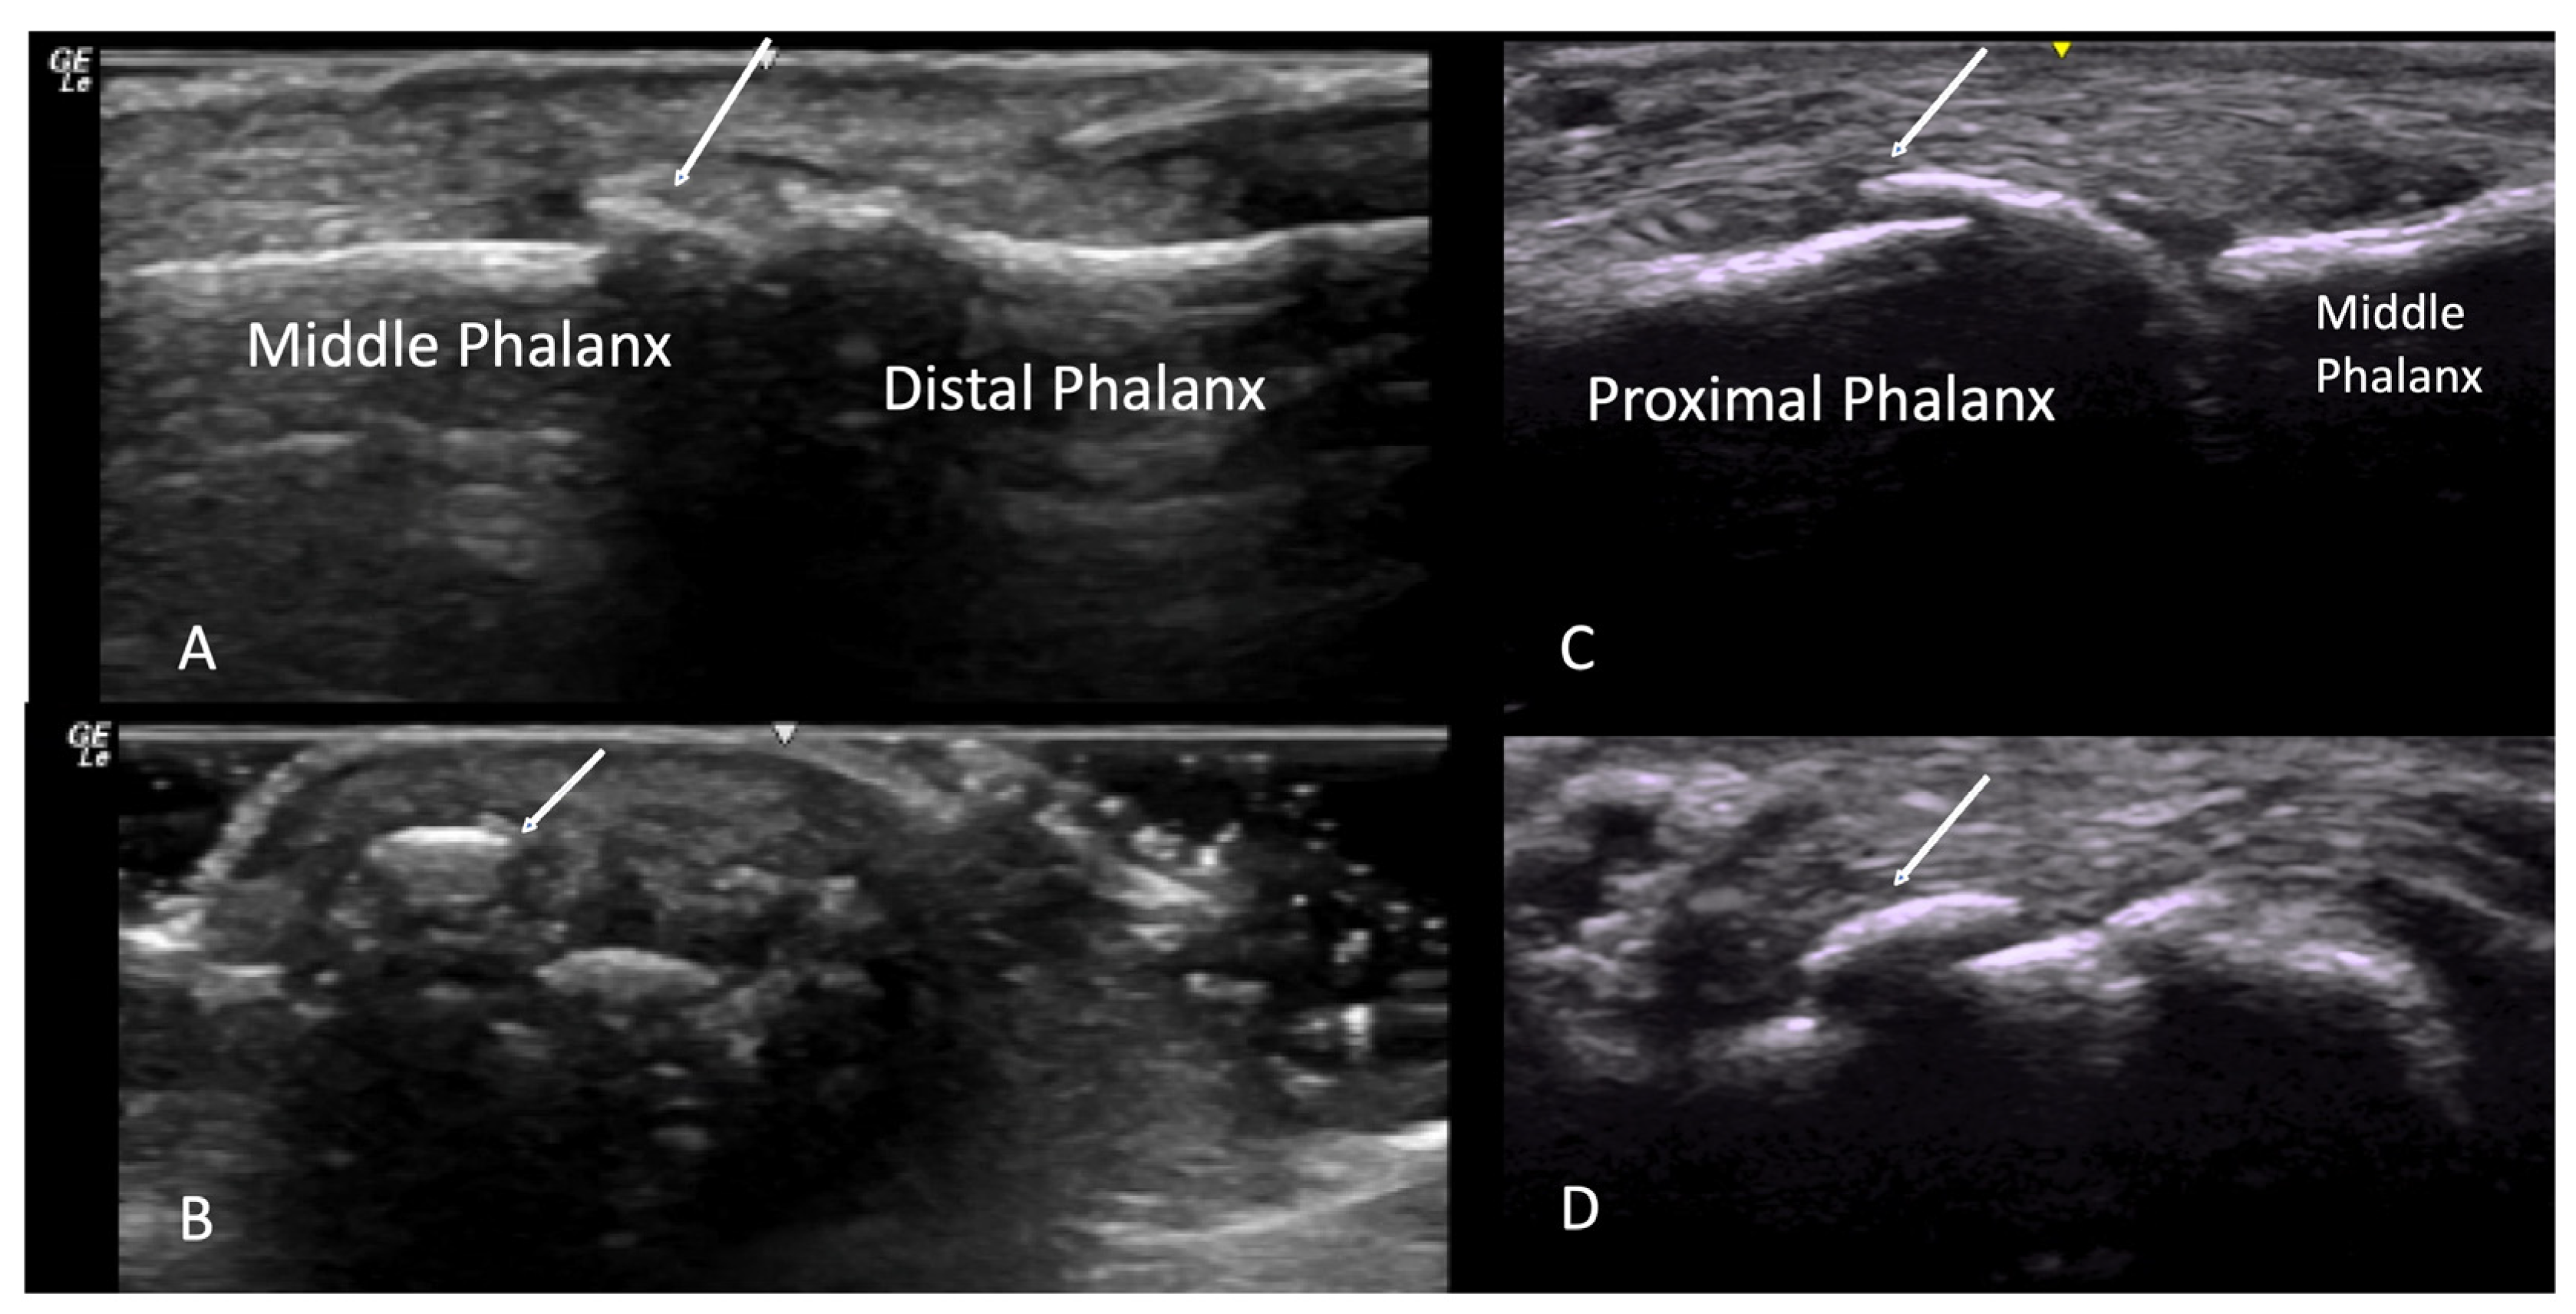

2.1.3. Acro-Osteolysis

2.6. Calcium Deposition

3. Materials and Equipment